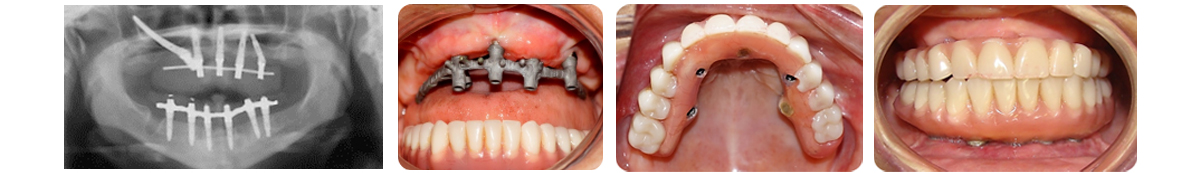

Son componentes sanitarios de titanio diseñados para sustituir el diente perdido que se instalan quirurgicamente en el hueso de los maxilares y malares, tienen forma roscada y estan fabricados con materiales biocompatibles que no producen reacción de rechazo y permiten su unión al hueso, los cuales ayudan a completar nuevamente la dentadura, dando un diente artificial que se ve estéticamente bien y que cumple con todas las funciones masticatorias que se necesita como si se tratara de un diente natural

IMPLANTES UNITARIOS CON CARGA INMEDIATA:

Son situaciones clínicas que en el acto quirúrgico de exodoncia del diente se coloca inmediatamente el implante dental y se rehabilita o entra en función con la confección de una corona o funda provisional: